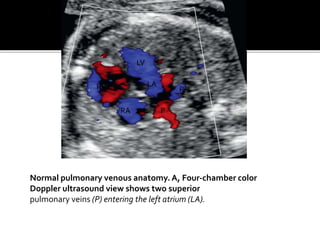

Normal pulmonary venous anatomy. A, Four-chamber color

Doppler ultrasound view shows two superior

pulmonary veins (P) entering the left atrium (LA).

Normal pulmonary venousanatomy. A, Four-chamber color Doppler ultrasound view shows two superior pulmonary veins (P) entering the left atrium (LA). RV LV RA LA P P